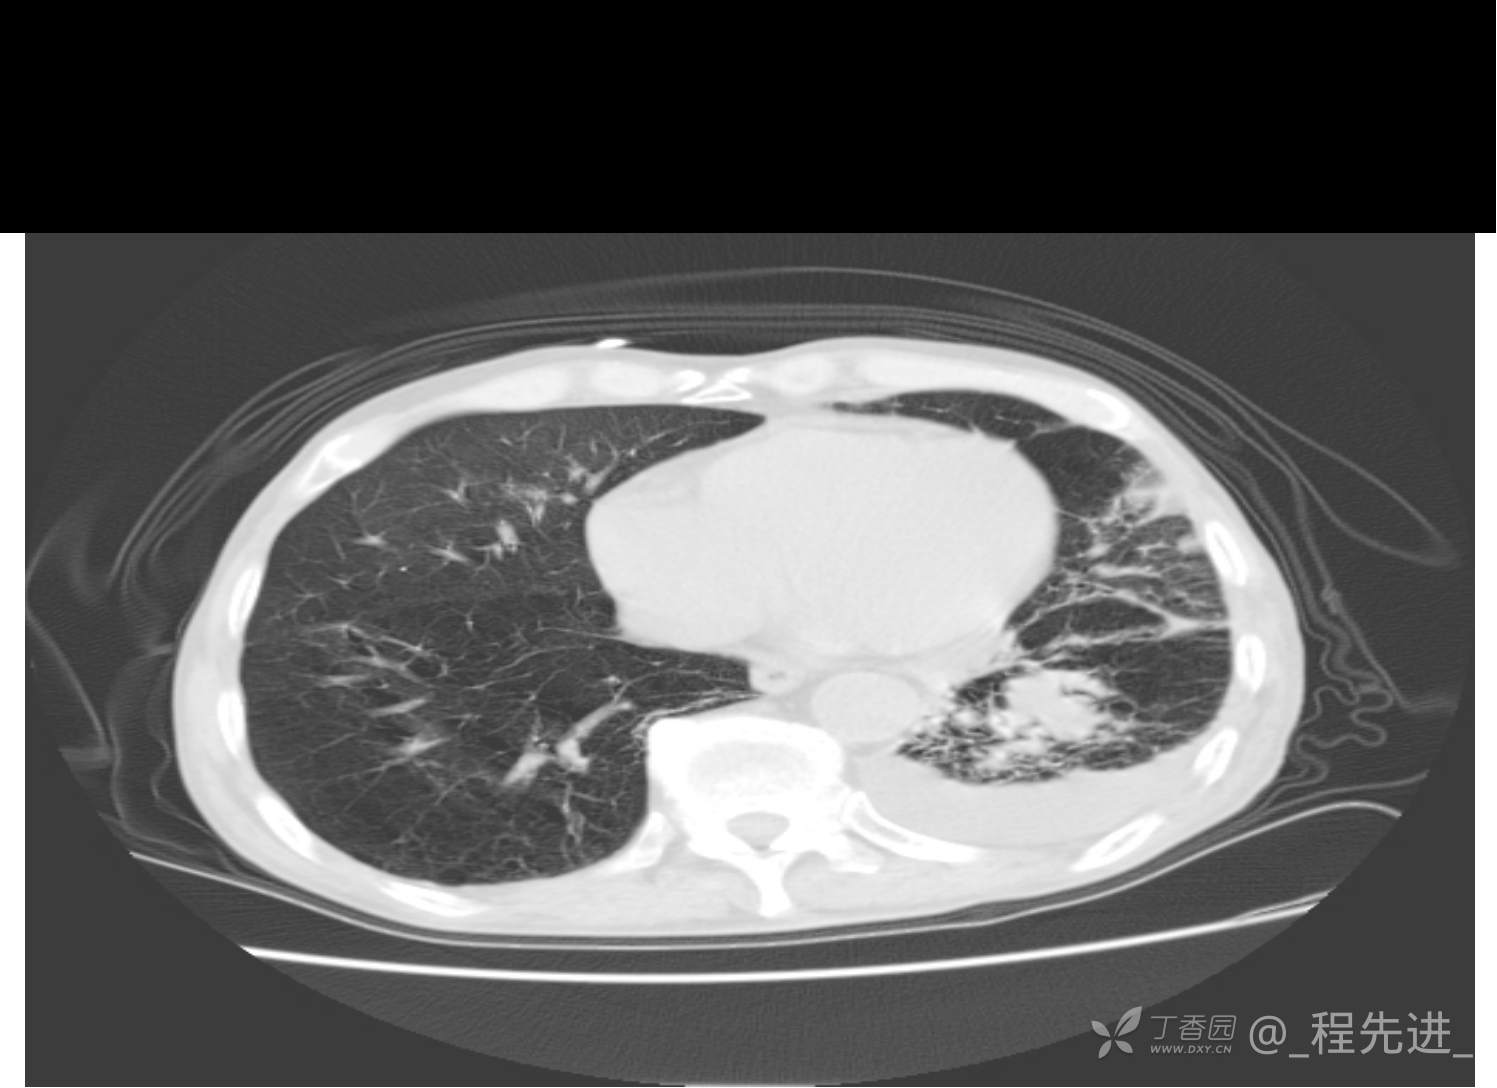

患者性别:男

患者年龄:81岁

简要病史:反复咳嗽、咳痰20余年,加重1周。两肺呼吸音低,可闻及散在干湿啰音。